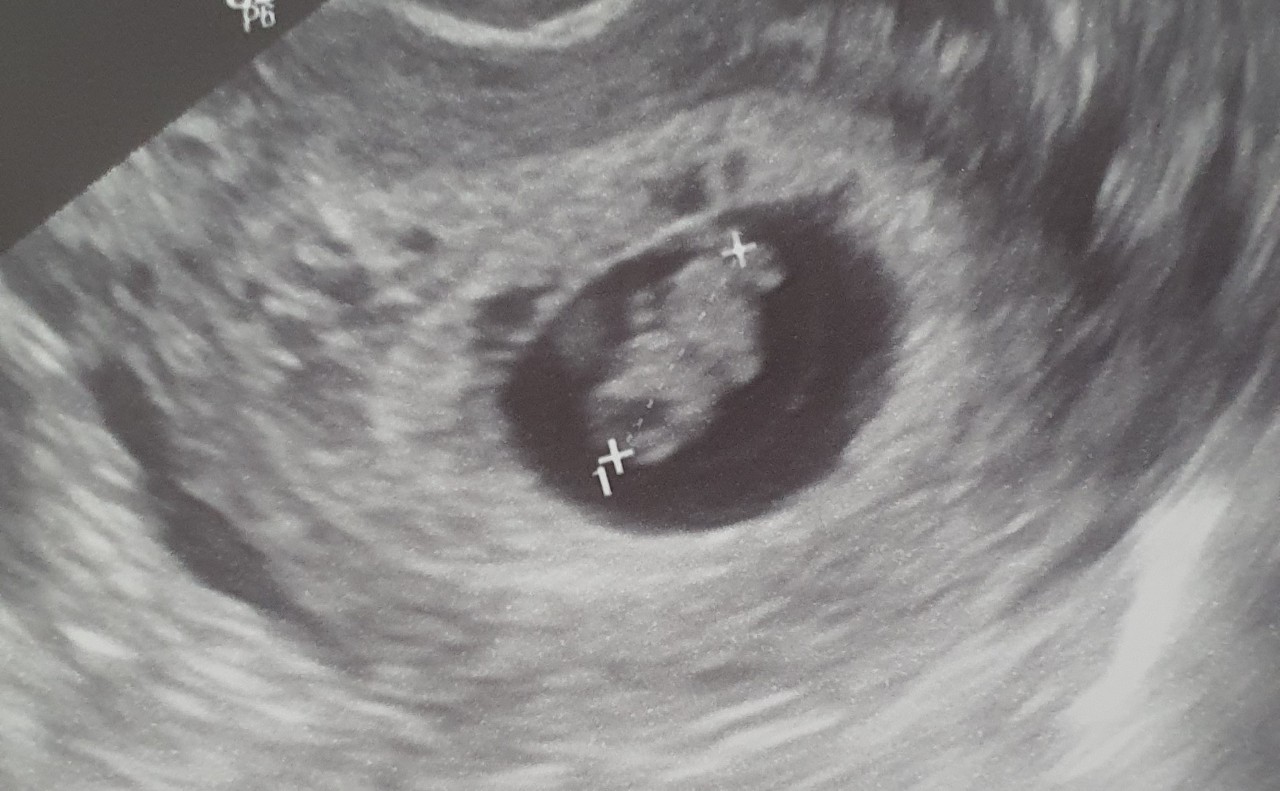

Развитие эмбриона на 8 неделе беременности